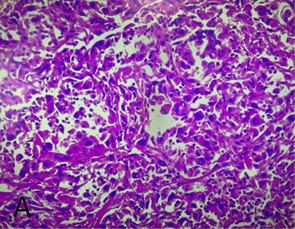

Figure 2. Histological findings

A: h/e stain, tumor shows moderate atypical spindle cells

forming fascicles and rhabdoid features with no epithelial component, b: pax8

slide, c: positive for vimentin

Renal nuclear scan (99 m mag3 scan) showed negligible right kidney function, which supported the decision to proceed with nephrectomy. Pathological exam of the right radical nephrectomy showed poorly differentiated sarcomatoid renal cell carcinoma with focal rhabdoid features, involving the right entire kidney with extension into the renal sinus and perirenal fat with extensive necrosis, focal tumor invasion into the renal vein, but not lumen, negative extension into the adrenal gland and ureteral resection margin with staghorn calculus of the renal pelvis with abscess formation.

Positive right

retroperitoneal lymph node for poorly differentiated sarcomatoid, and rhabdoid

rcc, infiltrating, fibroadipose tissue and regional blood vessels. Tumor

markers with positive for, ck7, vimentin, ae1/ae3, pax8, cd10, negative for

ck20, rcc, p40, gata-3. Pathological

stage pt3a n1, mx (figures 1 and 2)